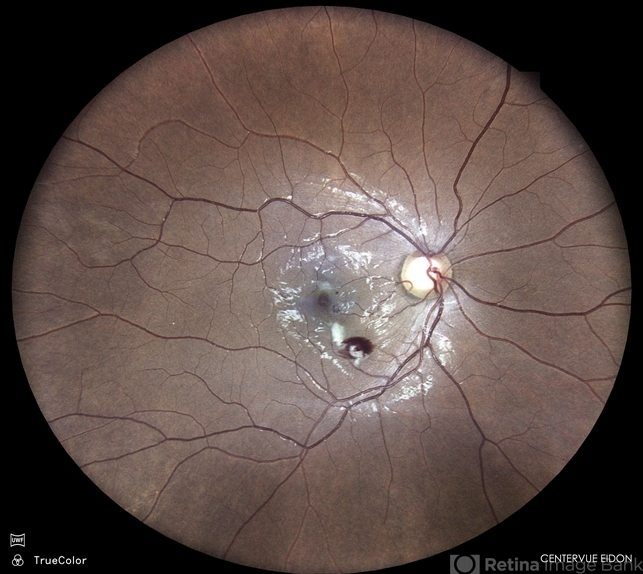

- retinitis, cotton wool exudates

- Dr. Akansha Sharma, Bharati Eye Hospital

- Imaging device

- Scanning laser ophthalmoscope

- Color fundus photograph of a 32 year old male patient presenting with retinitis post fever.